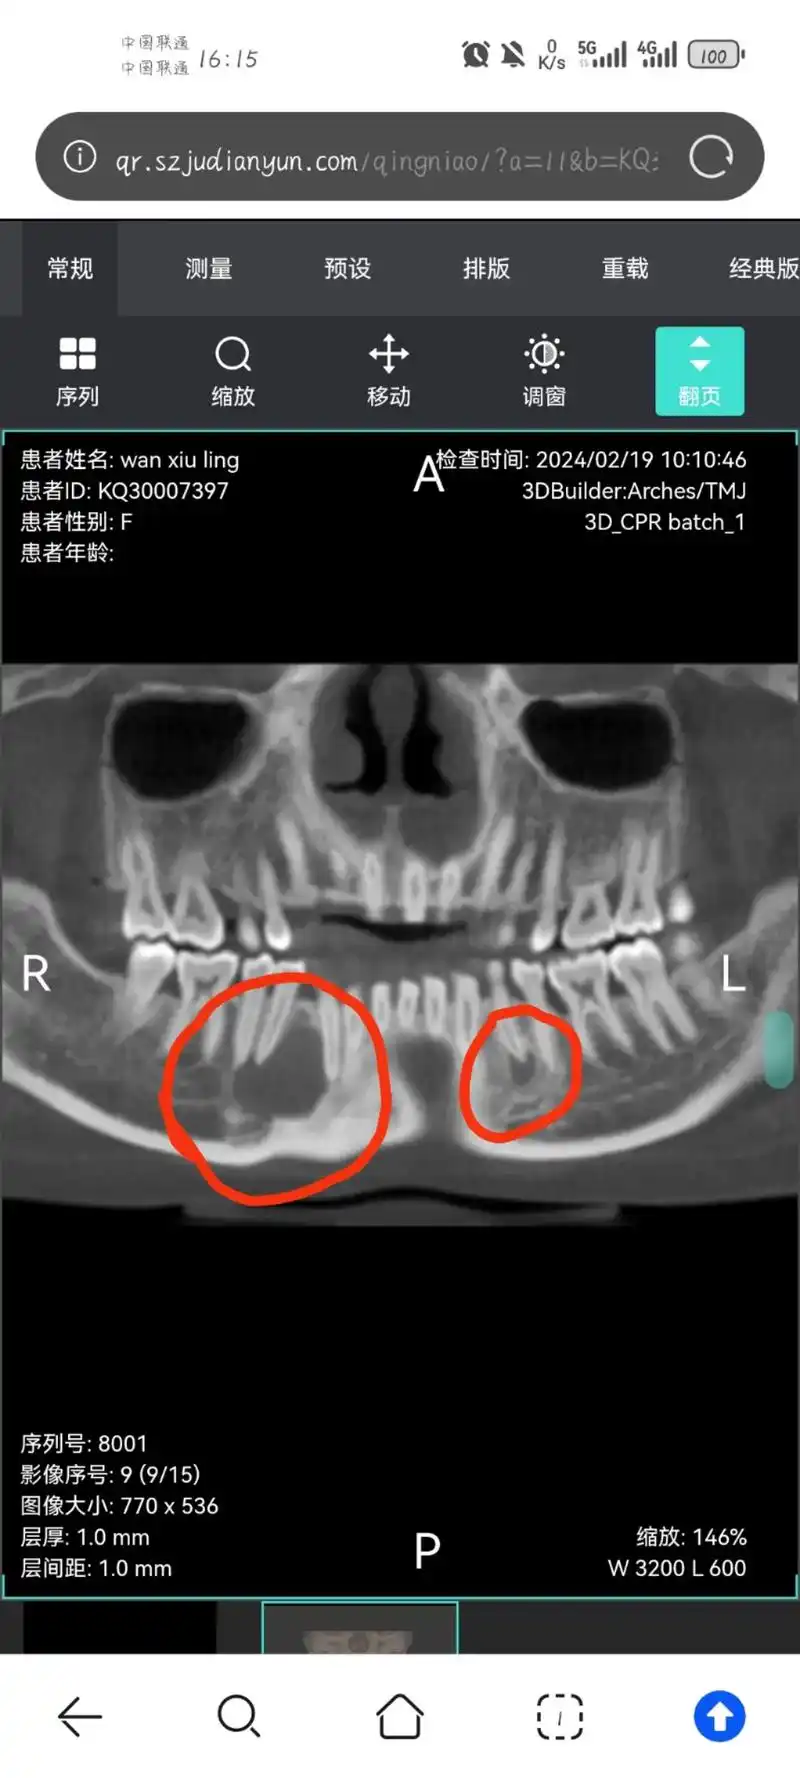

补牙之后想要拔智齿,拍完ct后,发现红圈圈的地方疑似囊肿,建议去公立

原本去拍ct拔智齿的,结果发现两个根尖囊肿,好像要手术,牙齿 - 抖音

泰安中心医院口腔颌面外科做了btct,确定了左下颌,右下颌两颗含牙囊肿